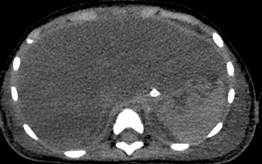

Los estudios de laboratorio iniciales (Tabla 1) del 26 de abril de 2024 mostraron resultados alarmantes, incluyendo anemia normocítica normocrómica arregenerativa, leucopenia severa, neutropenia severa, linfopenia moderada, trombocitopenia severa, hipertrigliceridemia, hiperferritinemia e hipofibrinogenemia. Los marcadores inflamatorios estaban extremadamente elevados, con una PCR de 23.9 mg/dL, LDH de 3322 U/L, y ferritina de 3028 ng/mL. Los niveles de triglicéridos eran de 698 mg/dL, sugiriendo un estado inflamatorio sistémico severo. Las enzimas hepáticas (TGO 1337 U/L, TGP 545 U/L) y bilirrubinas totales (2.88 mg/dL) confirmaron el compromiso hepático significativo. Además, el tiempo de protrombina prolongado y la no coagulación en TTP indicaban coagulopatía. Estudio de tomografía simple de abdomen con evidencia de hepatomegalia y ascitis. Las pruebas virológicas revelaron una alta carga viral de Epstein-Barr (7479014 copias/mL en sangre y 320910 en médula ósea), junto con una infección concomitante por CMV (250 copias), mientras que las pruebas para HIV y tuberculosis fueron negativas. En el mielograma se evidenció hipocelularidad medular con hemofagocitosis evidente, consolidando el diagnóstico de linfohistiocitosis hemofagocítica (HLH) secundaria a infecciones por VEB y CMV (Figura 1 y 2).

Figura 3.

Tomografía simple de abdomen con hepatomegalia.